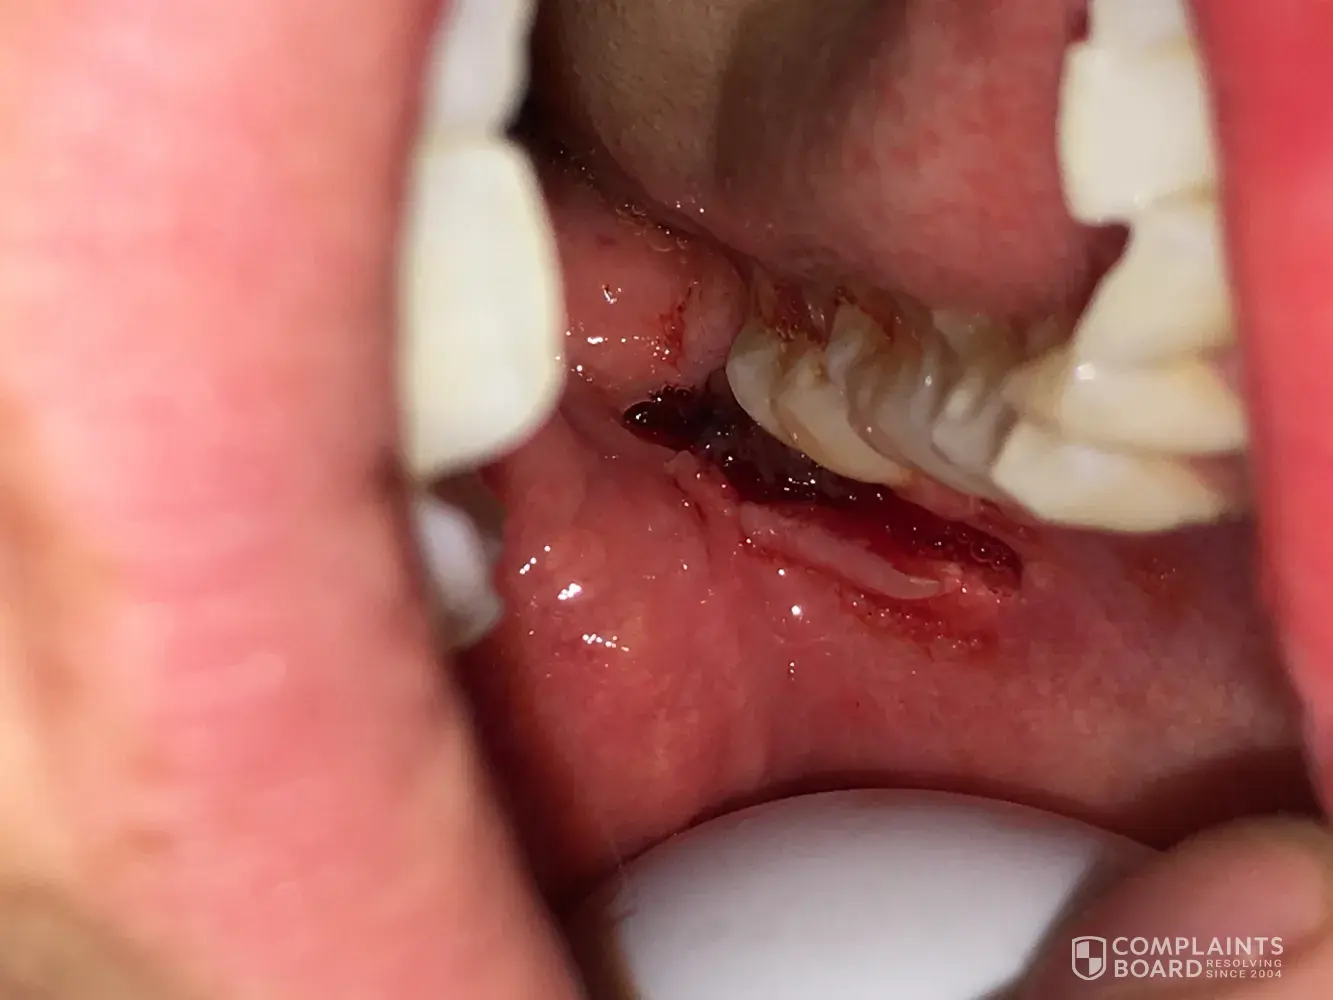

Aspen Dental Wisdom tooth removal

I went to the Aspen Dental in Alton, IL to get all four of my wisdom teeth extracted. I had never had dental work before so I was already petrified. I went in for my appointment, watched as literally everyone in the waiting room got taken back before me. I waited 3 hours past my appointment time with no explanation. Finally, they called me back, they ran my card for the $700 procedure. Took me back to the room, used the numbing gel, and left me in the chair for 45 minutes "waiting for the numbing to work". they finally came into the room to use the numbing injections, they were extremely rough and I felt every shot. I had tears rolling at this point. They started the process with the dental assistant physically holding my head down while the surgeon yanked and pulled. All of a sudden, they both stopped stood up and said we will be right back we need to grab some equipment. I waited. They came back into the room, the surgeon says, "I have to go, we will have to reschedule you for a different time". the assistant handed me my purse and sent me on my way. I was balling at this point trying to explain to my boyfriend what happened but my mouth was numb. I was spitting out blood in the parking lot. I wasnt offered any ice, gauze, pain meds, nothing. they were in shock that I was upset. If this wasnt bad enough, once I got home and the swelling and numbing went down I was in extreme pain. I looked in the mirror to find a gaping incision in the back of my mouth. so the surgeon had actually made the incision to extract the tooth, then sent me on my way...no stitches, no packing, no gauze, no pain meds. Then no other dentists would touch my mouth because they didnt want to be held liable for something they didnt originally do, so I had to wait until it healed on its own. I sent a very strong worded email, never got any type of response. it took some fighting but I did end up getting my $700 back. it was a traumatizing experience. I would never recommend this company to ANYBODY.